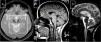

Marinesco-Sjögren syndromeThis condition is caused by mutations to the SIL1 gene (5q31.2), which codes for a nucleotide exchange factor for HSPA5, a heat-shock protein 70 (HSP-70) chaperone.60 Symptoms include short stature, hypergonadotropic hypogonadism, skeletal deformities, myopathy, congenital cataracts, and cerebellar ataxia; MRI studies display marked atrophy (Fig. 3).

MR images from a patient with Marinesco-Sjögren syndrome. A) Sagittal T1-weighted sequence showing atrophy of the brainstem and cerebellar vermis. B) Axial T2-weighted sequence showing atrophy of the pons, vermis, and both cerebellar hemispheres, with no intraparenchymal signal alterations.